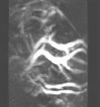

Fig. 9: 3D TCT image of vasculature in the head of a mouse

In order to capture sufficient thermoacoustic data to form an accurate 3D map of electromagnetic absorption, it is necessary to surround the anatomy being imaged with a 2D array of transducers. The world's first 3D thermoacoustic animal scanner (Fig. 8: left panel) accomplished this by combining a cylindrical array of 128 transducers (Fig. 8: center panel) with rotation of the animal being imaged about the vertical axis. The net result was to capture thermoacoustic data over the surface of a sphere surrounding the animal being imaged (Fig. 8: right panel).[21] This device was capable of visualizing structures as small as 1/3 millimeter. An animated 3D image of the vasculature in the head of a mouse is displayed in Fig. 9. This animated image was acquired using near infrared radiation at 800 nm, where optical absorption by blood is higher than surrounding tissues. Therefore, the vasculature is preferentially visualized. Microwaves have also been used to form 3D thermoacoustic images of the human breast. One of the first devices to do so is depicted in Fig. 10. It consisted of an array of eight waveguides, which directed microwave energy into the breast. A transducer array was rotated in synchrony with the waveguides in order to acquire sufficient data to reconstruct the internal structures of the breast. Figure 11 shows an animation of the typical glandular tissue pattern in a normal breast.